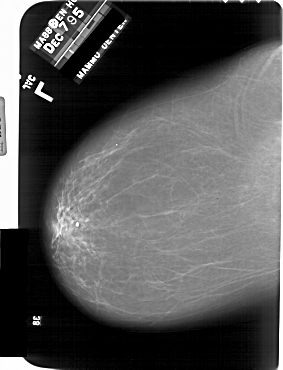

A_1863_1.RIGHT_MLO

RIGHT_MLO LINES 6586 PIXELS_PER_LINE 5131 BITS_PER_PIXEL 12 RESOLUTION 43.5 OVERLAY